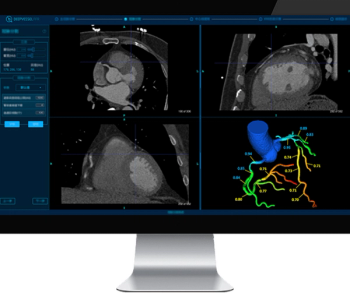

Comparing year-long findings with and without adjunctive artificial intelligence (AI) at a breast cancer screening program in Spain, researchers found the combination of digital breast tomosynthesis and AI had a 92.5 percent accuracy for diagnosing cancer in patients with elevated risk.